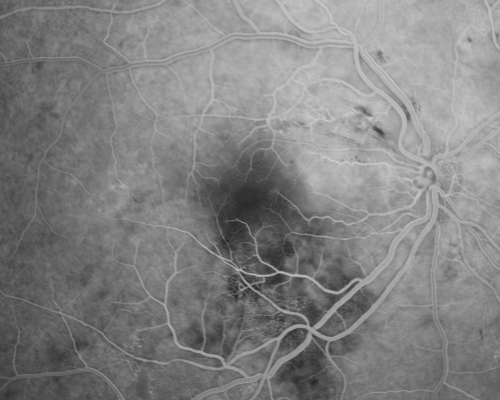

Hypertensive Retinopathy with Choroidal Ischemia Right Eye and Vision 8/200 - Blood Pressure 240/120 mmHg IgA Nephropathy

39-year-old man two days ago he noticed poor vision in his right eye OD: 8/200; OS: 20/20. BP is 240/120